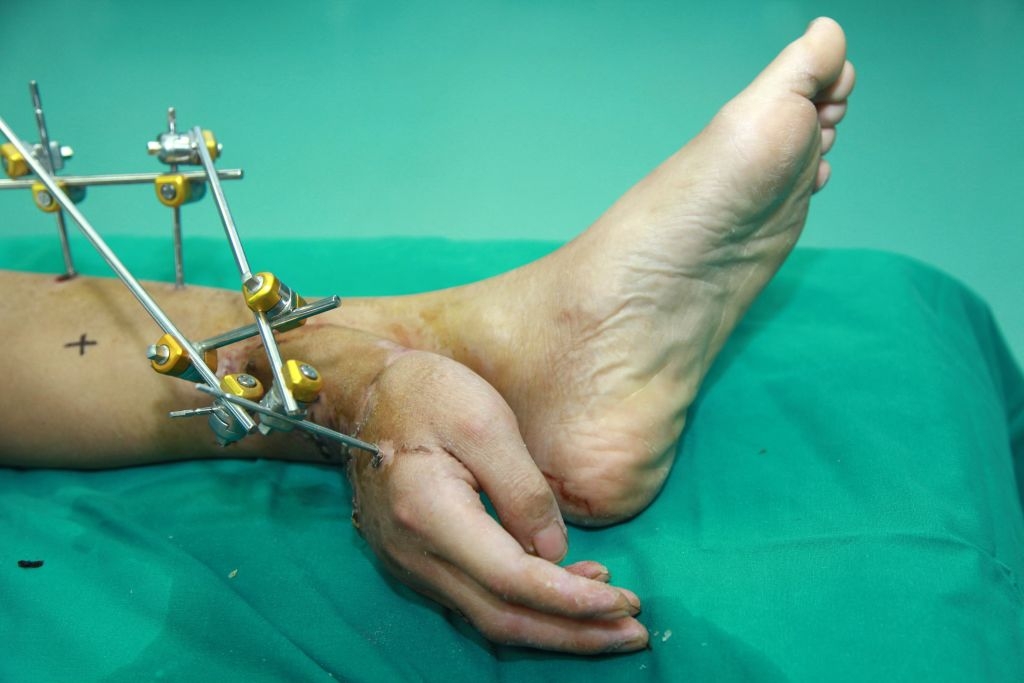

5.Did you know that a severed hand can be saved by sewing it to another body part? That’s what doctors did with Chinese patient Xie Wei. Doctors were unable to immediately reattach his hand (which had been severed in a work accident) to his arm, so they temporarily attached it to his leg to use the blood supply of the arteries there.

6.Here’s another photo. And don’t worry — the hand was later reattached to Wei’s arm!